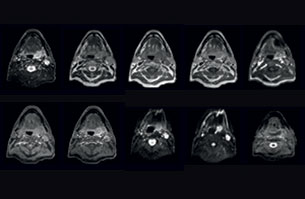

A 63-year-old patient with prostate cancer, cT3bNxM, Gleason 7, underwent MRI on Ingenia 3.0T MR-RT before radiation therapy.

Intraprostatic lesions are visible on the bTFE MR image, but not on the CT image. MRI shows excellent soft-tissue contrast for the visualization of critical structures like the rectum and penile bulb.

Fiducial markers (green arrows) are used in registration of MR images to CT, to transfer the MR-based delineations onto the CT image dataset.